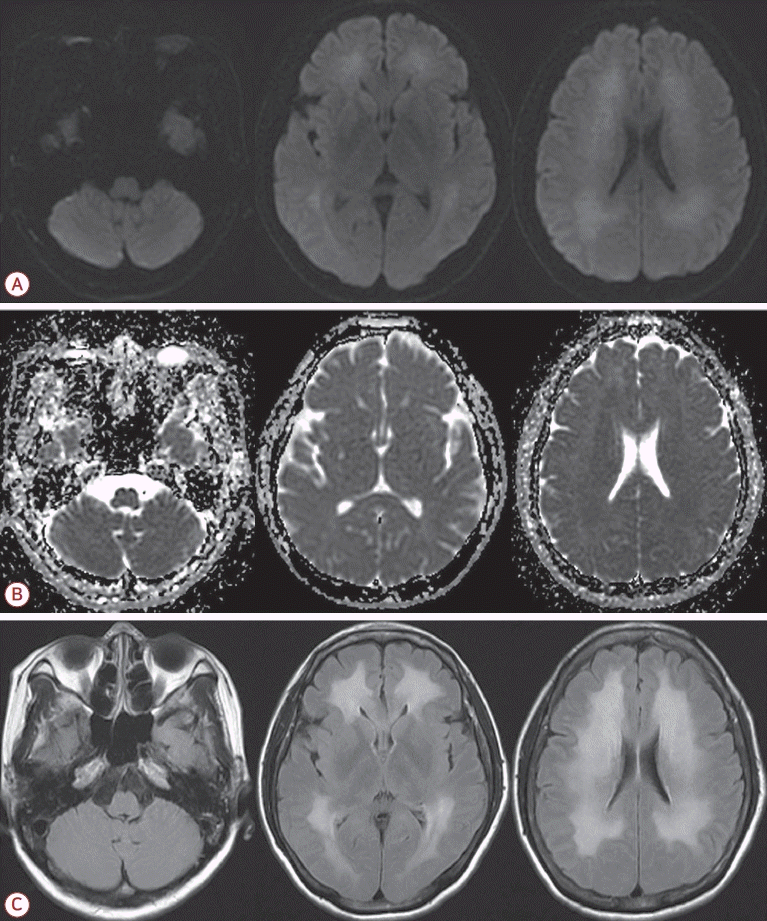

내원 당일 시행한 확산강조영상에서 양측 소뇌의 수평틈새 인근의 소뇌이랑에 대칭적인 고신호강도의 병변이 관찰되었다(Fig. 1-A). 이 병변은 겉보기확산계수지도영상에서는 저신호강도를 보였고(Fig. 1-B) 액체감쇠역전회복영상에서는 고신호강도를 보였다(Fig. 1-C). 그 외 다른 뇌 부위에서의 병변은 관찰되지 않았다(Fig. 1).

Brain magnetic resonance imaging of a patient with carbon monoxide poisoning. Diffusion-weighted imaging shows hyperintense lesions in the bilateral cerebellum along the horizontal fissure (A), corresponding to hypointensity on the apparent diffusion coefficient map (B), and hyperintensity on the fluid attenuated inversion recovery imaging (C). No abnormal signal changes are observed in other brain regions.